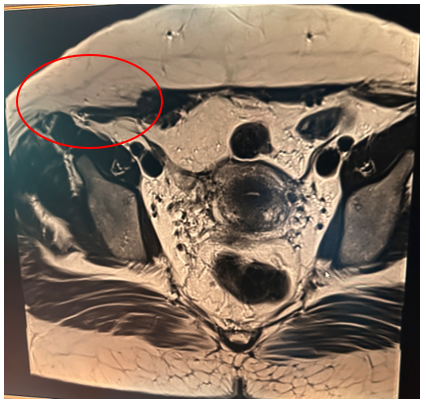

Thirty-eight-year-old patient, with two live children by caesarean section, consulting for Dysmenorrhoea and cyclic pelvic pain evolving for 6 months with, on clinical examination, an indurated mass measuring 4x3 cm opposite the external right side of the pfannestiel scar, pelvic ultrasound objectifying a deep, finely hypoechoic parietal nodular formation, measuring 32.7 x 12.7 mm, communicating with the pelvic cavity through a 4-mm diameter opening, suggesting an endometriotic nodule, followed on pelvic CT and MRI by a 35x20-mm nodular tissue mass of the rectus abdominis, suggesting parietal endometriosis (figure 1) associated with minimal subperitoneal endometriosis.

Figure 1.

Abdomino-pelvic CT scan showed an incisional supra-umbilical hernia with epiploic and uncomplicated digestive content, while pelvic MRI revealed soft-tissue nodules above and below the umbilicus, raising the initial suspicion of a parietal endometrioma (figures 3,4).

Figure 3-4: Soft tissue nodules above and below the umbilicus